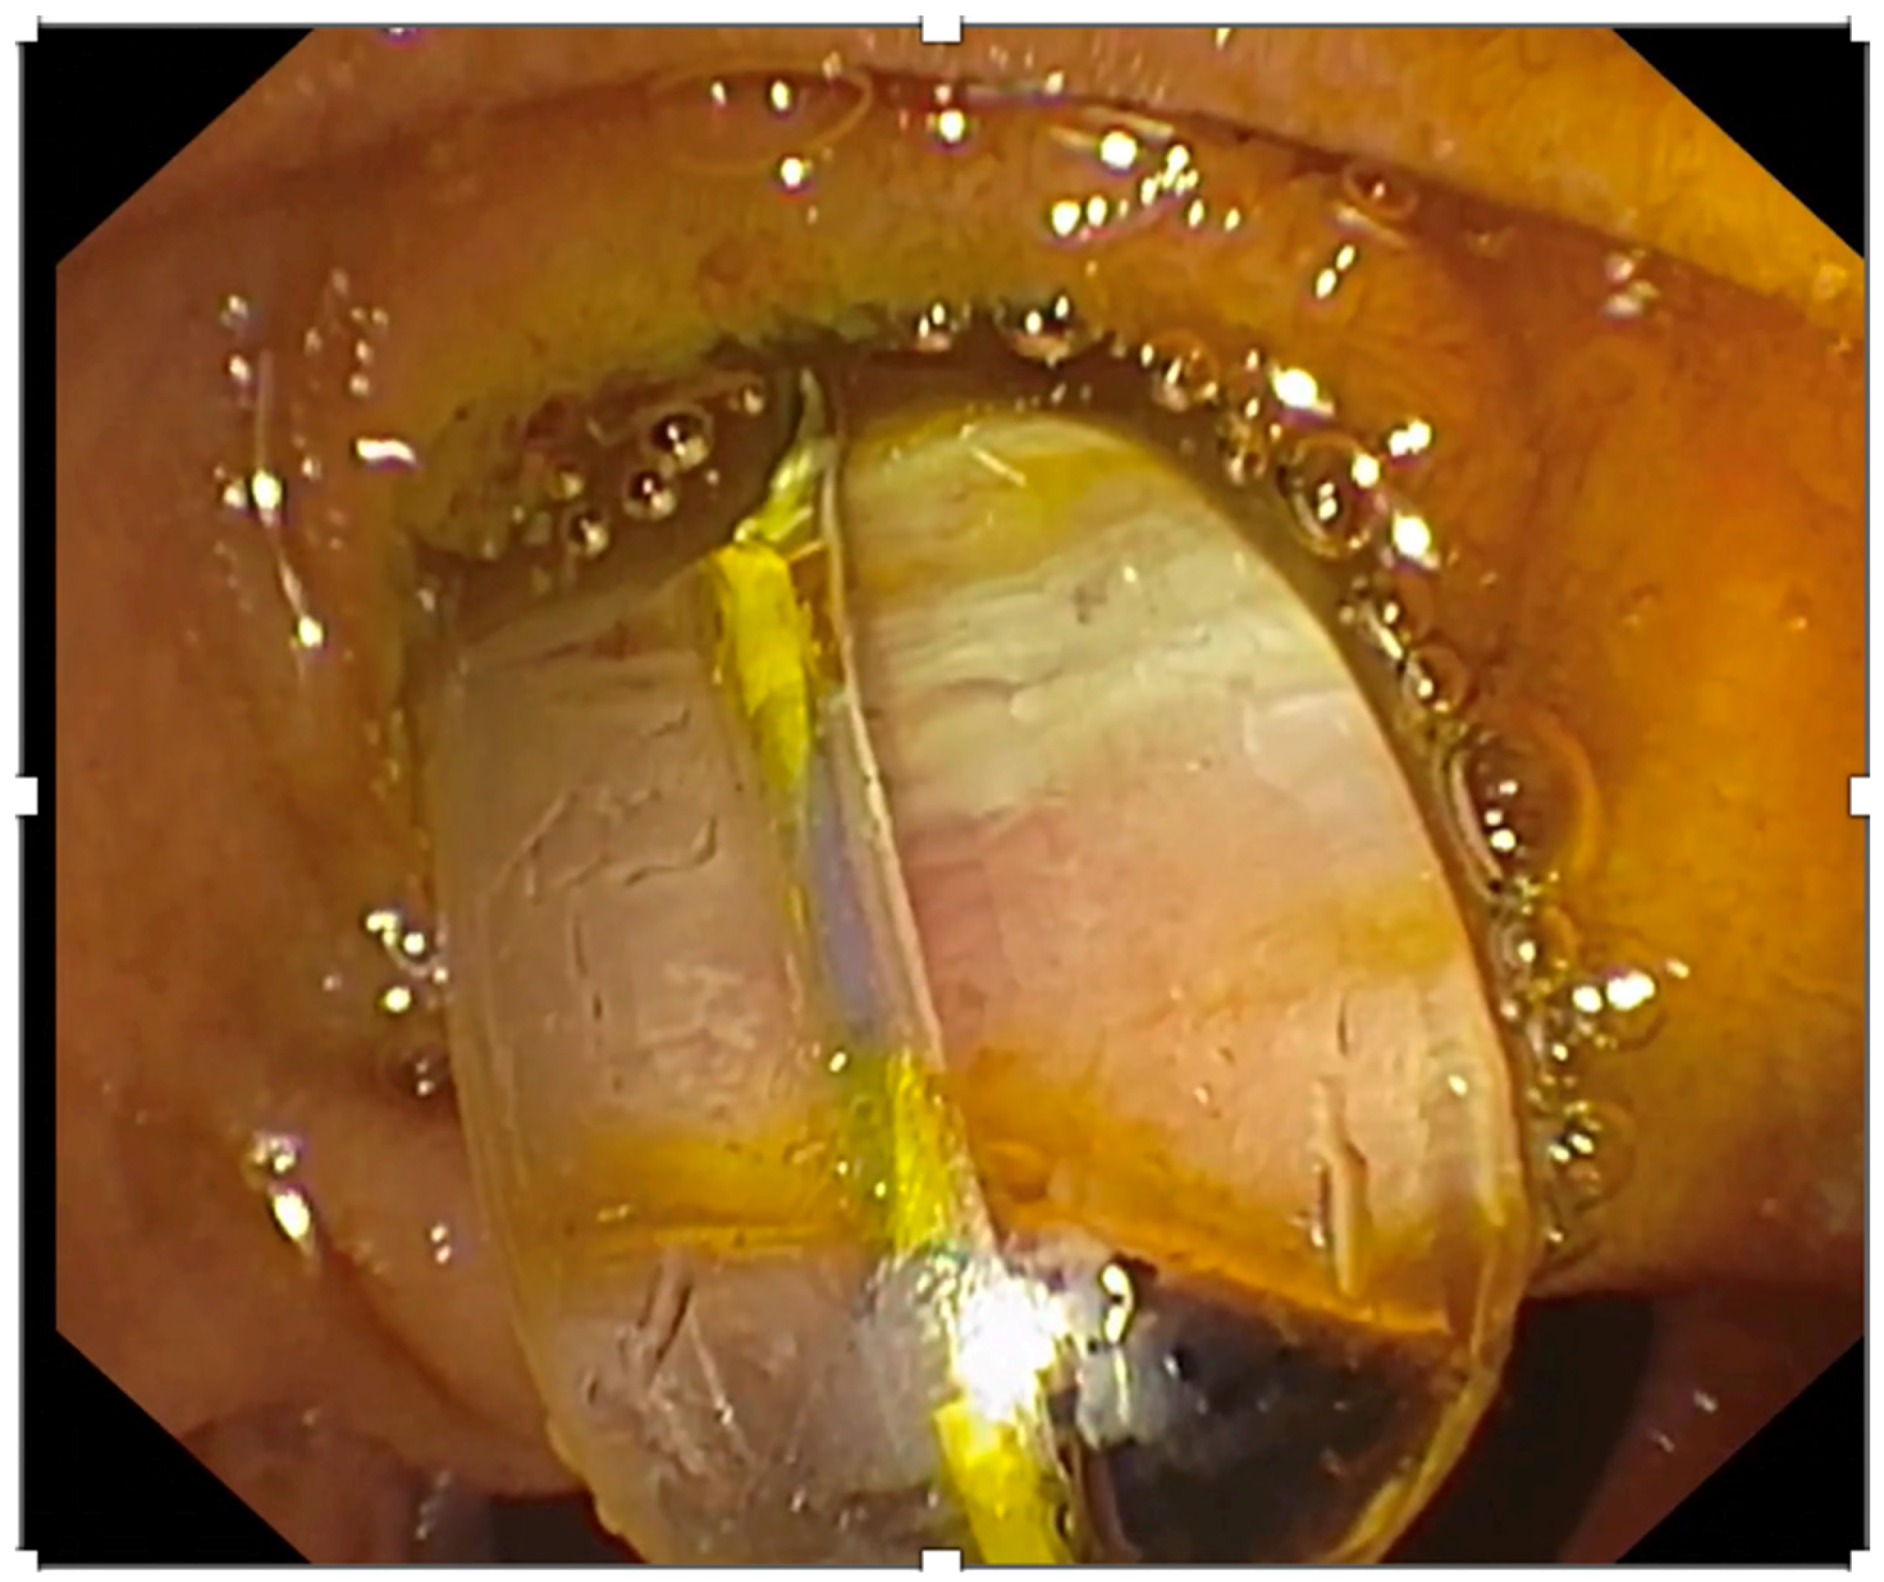

- Kamiyama, R.; Ogura, T.; Okuda, A.; Miyano, A.; Nishioka, N.; Imanishi, M.; Takagi, W.; Higuchi, K. Electrohydraulic Lithotripsy for Difficult Bile Duct Stones under Endoscopic Retrograde Cholangiopancreatography and Peroral Transluminal Cholangioscopy Guidance. Gut Liver 2018, 12, 457–462. [Google Scholar] [CrossRef]

- Angsuwatcharakon, P.; Kulpatcharapong, S.; Ridtitid, W.; Boonmee, C.; Piyachaturawat, P.; Kongkam, P.; Pareesri, W.; Rerknimitr, R. Digital cholangioscopy-guided laser versus mechanical lithotripsy for large bile duct stone removal after failed papillary large-balloon dilation: A randomized study. Endoscopy 2019, 51, 1066–1073. [Google Scholar] [CrossRef]

- Oh, C.H.; Dong, S.H. Recent advances in the management of difficult bile-duct stones: A focus on single-operator cholangioscopy-guided lithotripsy. Korean J. Intern. Med. 2021, 36, 235–246. [Google Scholar] [CrossRef]